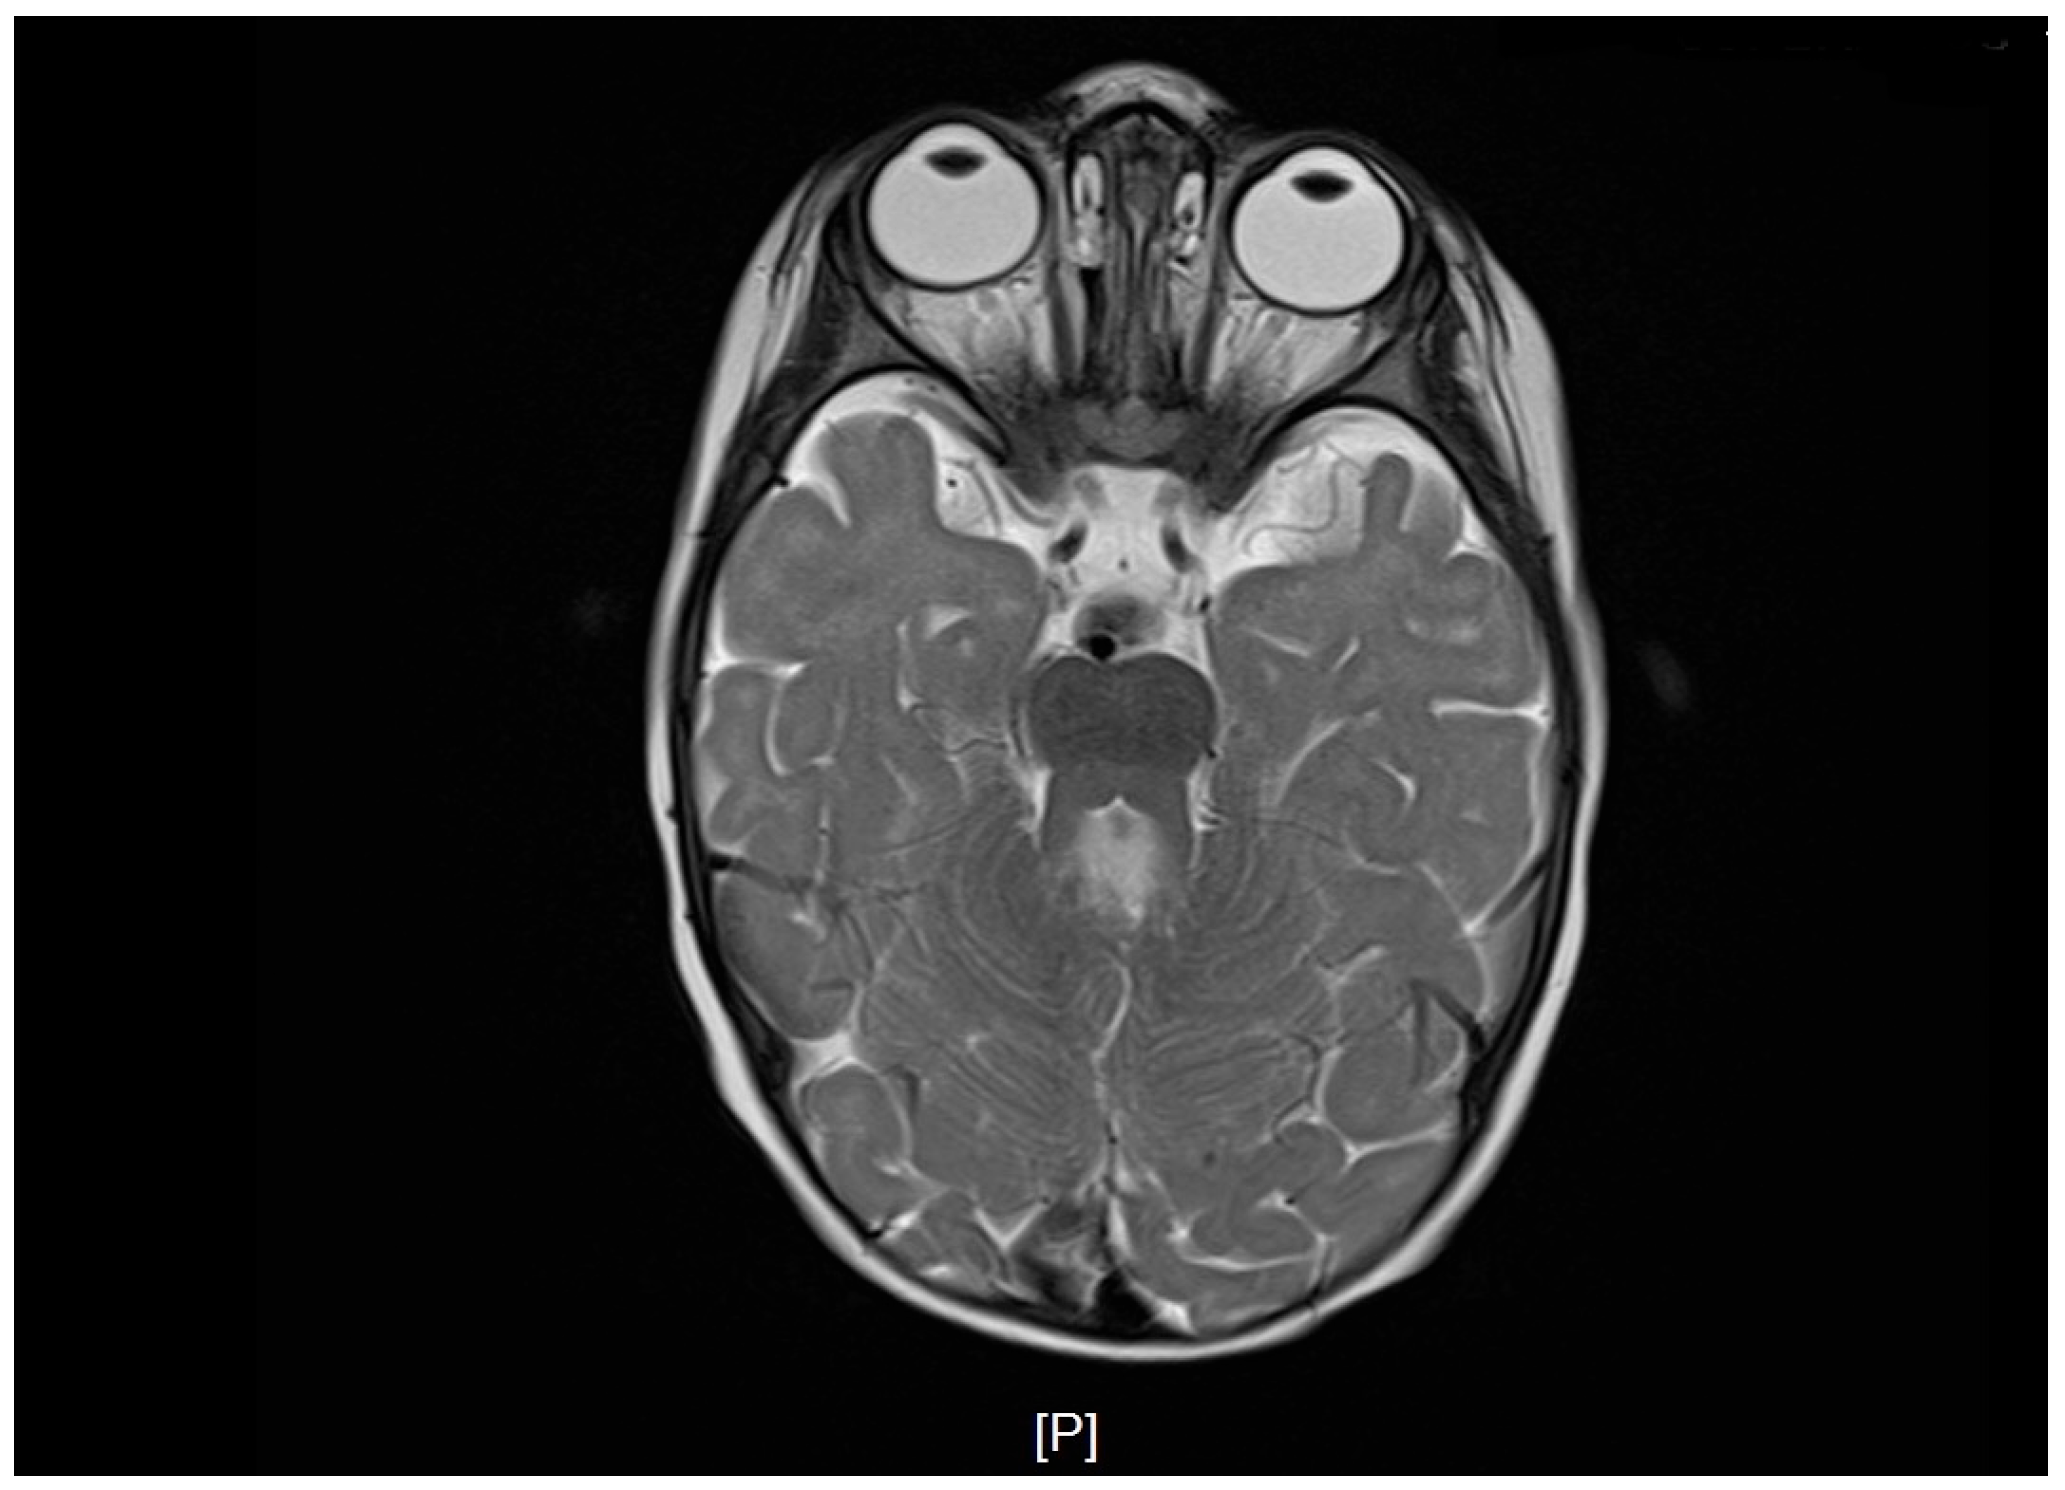

At 10 months of age, brain MRI revealed agenesis of the cerebellar vermis, thickened and elongated superior cerebellar peduncles, enlargement of the fourth ventricle with a batwing configuration, and a deepened interpeduncular fossa. These findings formed the molar tooth sign and were consistent with JS.

Postnatal brain MRI confirmed the diagnosis of JS based on the presence of the molar tooth sign (Figure 1). Polysomnography performed at 1 year of age demonstrated prolonged sleep latency (112 min), moderate mixed sleep apnea (AHI 5.4/h), and significant oxygen desaturation with a nadir SpO2 of 77%. Ophthalmologic follow-up confirmed persistent bilateral hyperopia with astigmatism requiring optical correction, consistent with cerebellar-related visual instability. Pelvic radiography performed at 2.5 years of age revealed asymmetric lateral migration of the femoral heads, more pronounced on the left side, with reduced acetabular coverage consistent with early subluxation (Figure 2). Clinically, the left lower limb presented with persistent adduction positioning. Diagnostic findings demonstrated cerebellar and brainstem abnormalities with direct functional implications for postural control, respiratory regulation, and motor development (Table 1).

Figure 1. Brain MRI demonstrating the molar tooth sign characteristic of Joubert syndrome. Axial T2-weighted image shows vermian agenesis and elongated superior cerebellar peduncles.